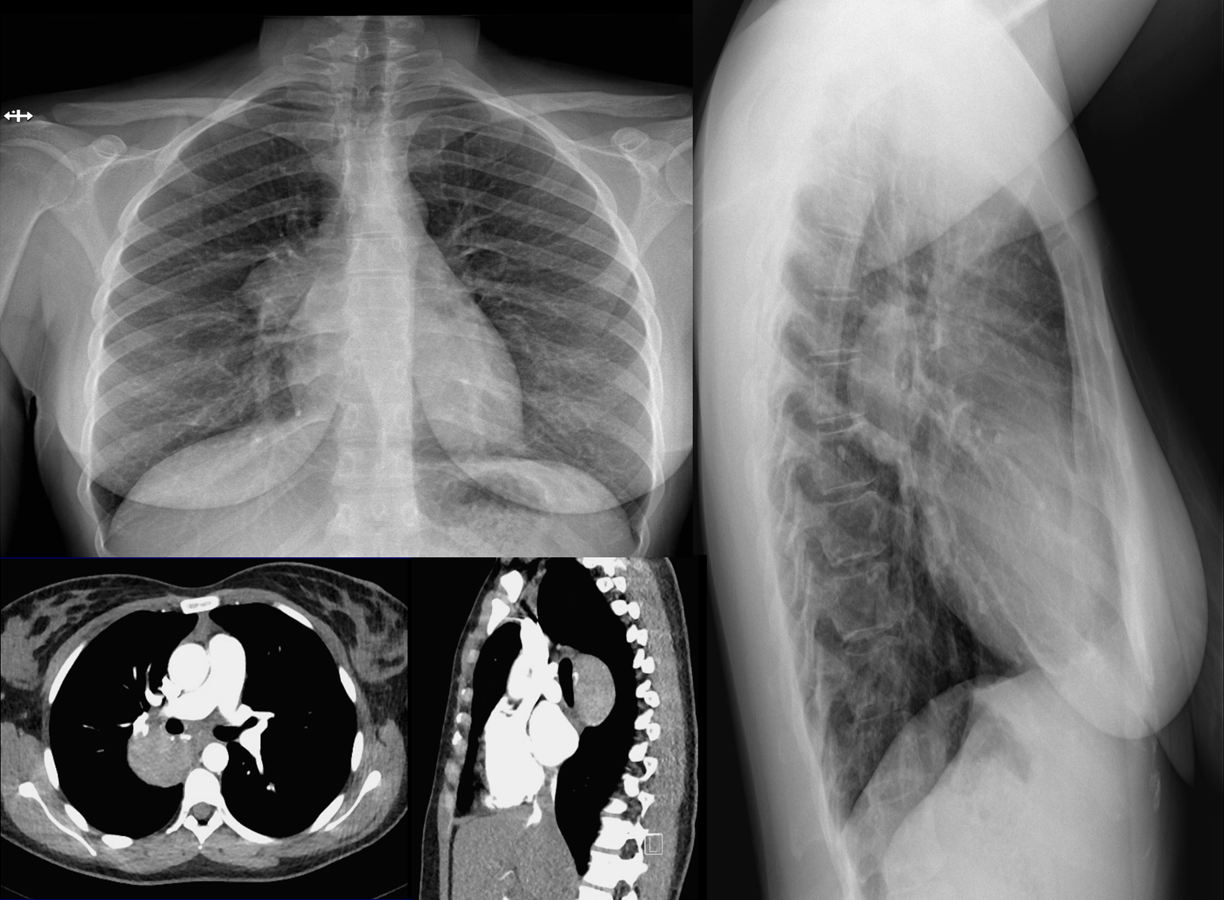

Femme de 28 ans

Douleur dorsale

Bilan réalisé:

Radiographie thoracique

Angioscanner

IRM

TEP-Scanner

QUEL EST VOTRE DIAGNOSTIC ?

A – PARAGANGLIOME

B – SCHWANNOME

C – CANCER BRONCHO-PULMONAIRE

D – MALADIE DE CASTLEMAN

E – METASTASE RÉNALE